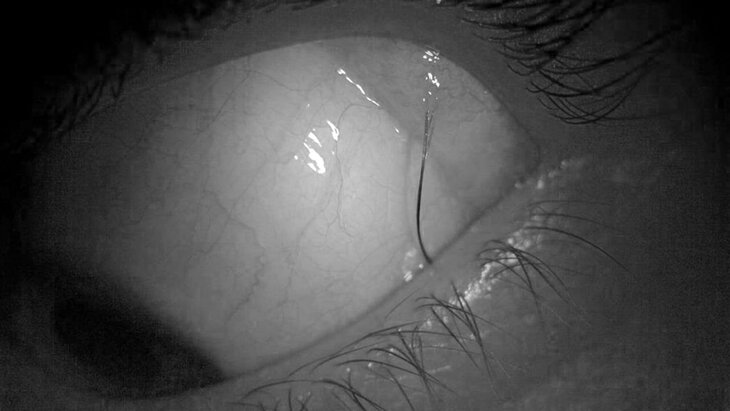

Врачи Детского клинического центра имени Л. М. Рошаля спасли 14-летнюю девочку, у которой в слизистой оболочке левого глаза вырос волос. Об этом сообщает "Радио 1" со ссылкой на пресс-службу подмосковного Минздрава.

Волос длиной примерно в 1 сантиметр был похож на ресницу, но находился в нетипичном месте и регулярно вылезал из-под века. Заведующий офтальмологическим отделением Максим Черников назвал такой случай редким, но не уникальным.

Врач уточнил, что липодермоида (врожденная доброкачественная опухоль конъюнктивы. – Прим. ред.) с аномальным ростом волос не представляла угрозы для ребенка, но постоянно вызывала дискомфорт. Именно поэтому новообразование было удалено, а волос – направлен на гистологическое исследование.